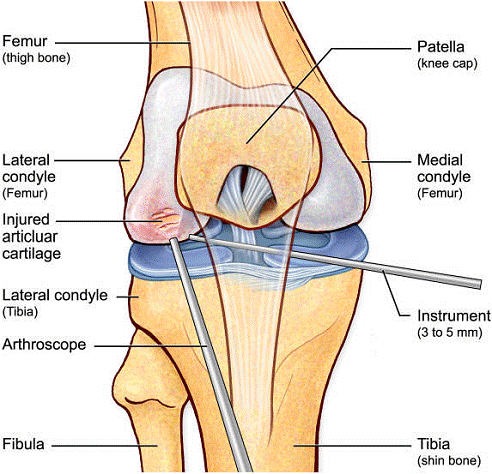

Artroscopia este o investigatie invaziva care permite vizualizarea foarte buna a spatiului articular cu ajutorul artroscopului. Artroscopul este format dintr-un endoscop cu fibra optica, instrument care se introduce direct in articulatie printr-o mica incizie subcutanata. Artroscopia ofera medicului posibilitatea de a inspecta suprafetele articulare si tesutul moale din jur: ligamentele si cartilajele.

Introducerea instrumentelor endoscopice permite nu numai examinarea in scop diagnostic a interiorului articulatiei, dar si tratarea leziunilor articulare sau indepartarea corpilor straini liberi din spatiul articular, fara a traumatiza sever tesuturile invecinate, cat si urmarirea evolutiei unei afectiuni articulare sau monitorizarea eficientei tratamentului.

Dupa o deschidere minima a articulatiei, practicata sub anestezie locala, medicul introduce artroscopul, tubul rigid dotat cu aparatura optica si instrumentele care permit realizarea chirurgiei intraarticulare. Majoritatea componentelor articulatiei sunt accesibile sub artroscopie: un corp strain articulatiei poate fi indepartat, un cartilaj - remodelat, iar un menisc recusut sau scos. In sfarsit, ligamentele pot face obiectul unor acte chirurgicale directe.

Un diagnostic de rutina de artroscopie este utilizat pentru a evolua toate compartimentele intra-articulare ale genunchiului. Inainte de efectuarea microfracturii, se raporteaza orice patologie intra-articulara asociata (cum ar fi de menisc).

Chirurgul trebuie sa fie foarte atent atunci cand examineaza posteriorul condililor femurali. Daca se semnaleaza orice vatamare/rana/deteriorare pe suprafetele articulare, trebuie sa se cerceteze atent calitatea cartilajului. Orice flapsuri instabile sunt inlaturate prin folosirea unui aparat de ras electric artroscopic sau curette. Apoi, un curette este folosit pentru a debrida stratul de cartilagiu calcifiat de la baza in toata grosimea defectului. Acest pas se bazeaza pe activitatea lui Frisbi, care a demonstrat vindecarea suprafetei articulare superioare la un cal, cand stratul cartilagiului calcifiat este indepartat. Cand indepartam stratul cartilajului calcifiat, in general nu se foloseste un aparat de ras. Cu un aparat de ras este dificil de controlat cantitatea de os eliminat, si este posibil ca osul subcondral sa fie afectat.